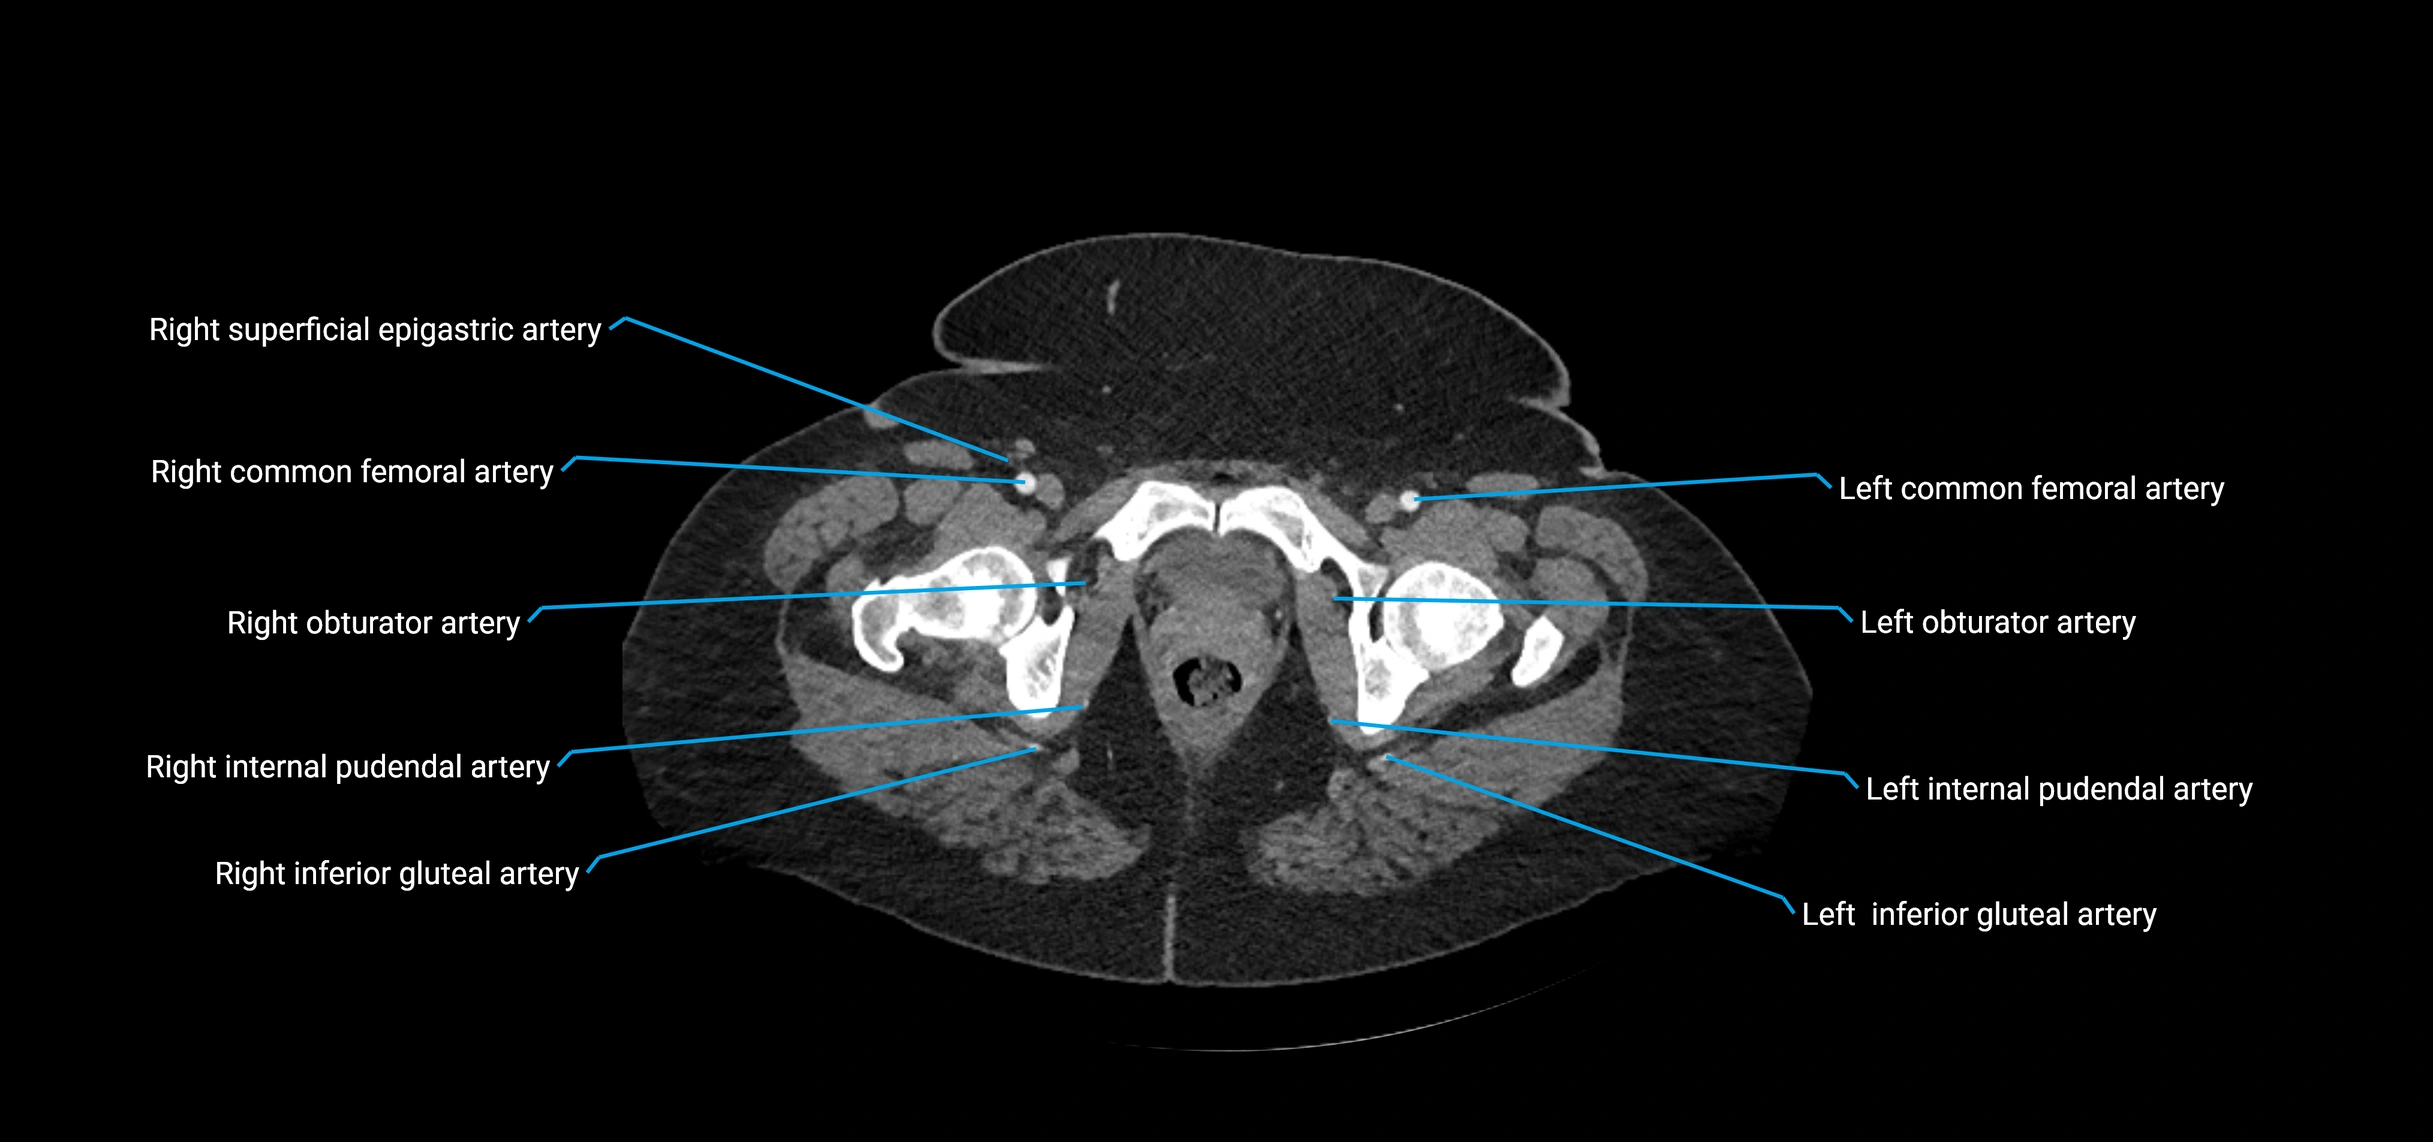

Contrast-enhanced CT (CTA):

• Gold standard for abdominal aortic imaging

• Provides excellent detail of lumen, wall, aneurysm, thrombus, and branch vessels

• Multiplanar and 3D reconstructions help in aneurysm measurement, stent graft planning, and dissection evaluation

• Detects acute rupture, traumatic injury, or occlusion with high sensitivity